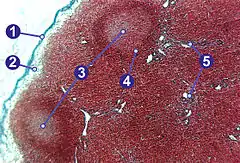

Cross-section of a lymph node with sections labelled.1) Capsule; 2) Subcapsular sinus; 3) Germinal centre; 4) Lymphoid nodule; 5) Trabeculae